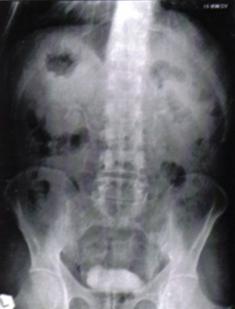

Fig.8 Imagini lacunare in aria vezicii urinare sugerand tumori vezicale superficiale [51].